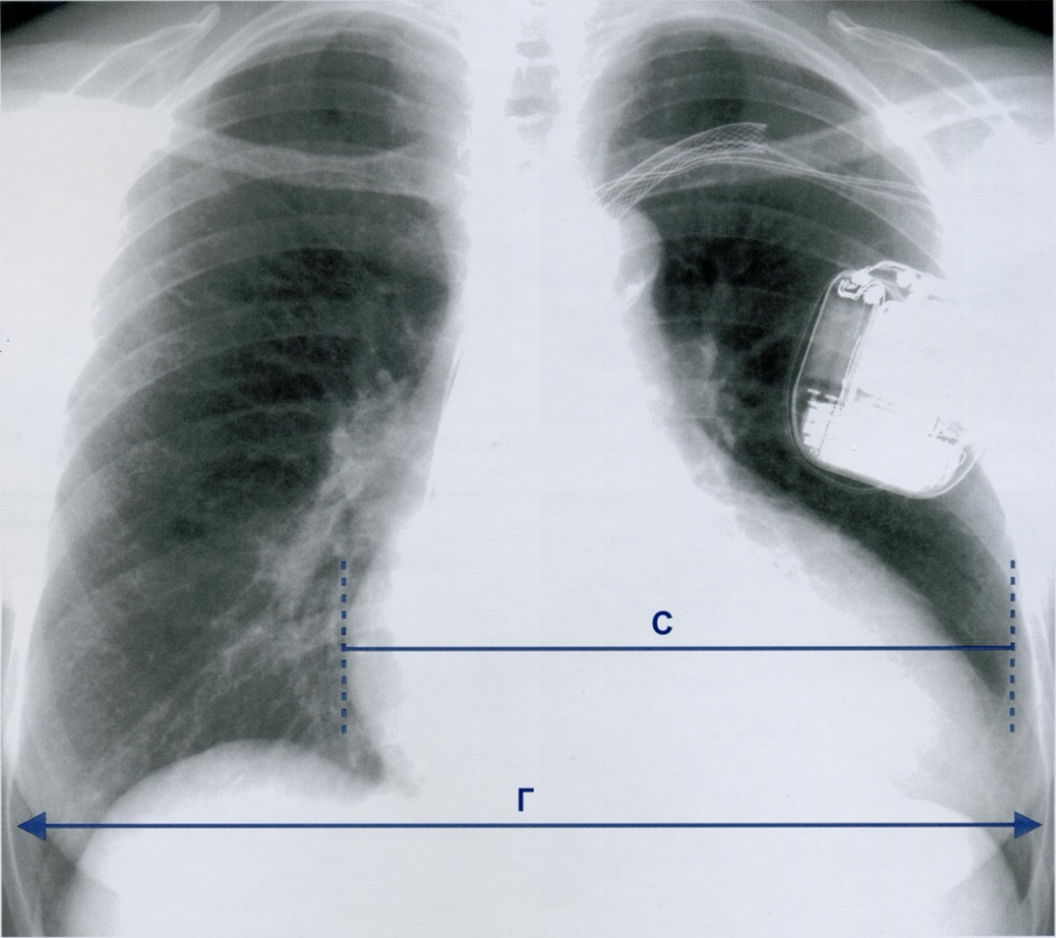

Что такое сердечно-грудной индекс (СГИ)?

Оцените СГИ на приведенном снимке.

Размеры тени сердца оцениваются по сердечно-грудному индексу (СГИ). Если СГИ больше 0,5 (снимок), говорят о кардиомегалии.

В приведенном примере максимальная ширина сердечной тени составляет 22,3 см (С), тогда как общий диаметр грудной клетки (Г) между внутренними латеральными краями ребер равен 33,5 см. Соотношение С/Г в этом случае (22,3/33,5) составляет 0,66, что подтверждает наличие кардиомегалии.